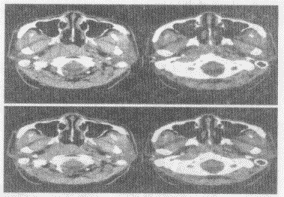

男,52岁,右耳鸣2个月余,伴鼻塞,CT如图所示,最可能的诊断是()A: 鼻咽淋巴瘤B: 鼻咽纤维血管瘤C: 增殖体肥大D: 鼻咽癌E: 鼻咽部慢性炎症

男,52岁,右耳鸣2个月余,伴鼻塞,CT如图所示,最可能的诊断是()